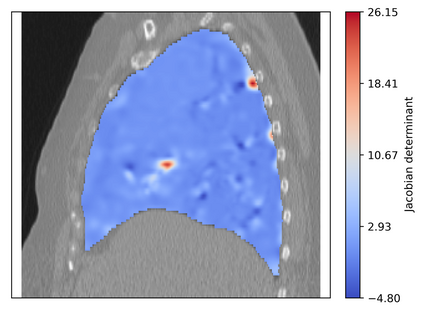

Deformable image registration is a fundamental task in medical image analysis and plays a crucial role in a wide range of clinical applications. Recently, deep learning-based approaches have been widely studied for deformable medical image registration and achieved promising results. However, existing deep learning image registration techniques do not theoretically guarantee topology-preserving transformations. This is a key property to preserve anatomical structures and achieve plausible transformations that can be used in real clinical settings. We propose a novel framework for deformable image registration. Firstly, we introduce a novel regulariser based on conformal-invariant properties in a nonlinear elasticity setting. Our regulariser enforces the deformation field to be smooth, invertible and orientation-preserving. More importantly, we strictly guarantee topology preservation yielding to a clinical meaningful registration. Secondly, we boost the performance of our regulariser through coordinate MLPs, where one can view the to-be-registered images as continuously differentiable entities. We demonstrate, through numerical and visual experiments, that our framework is able to outperform current techniques for image registration.